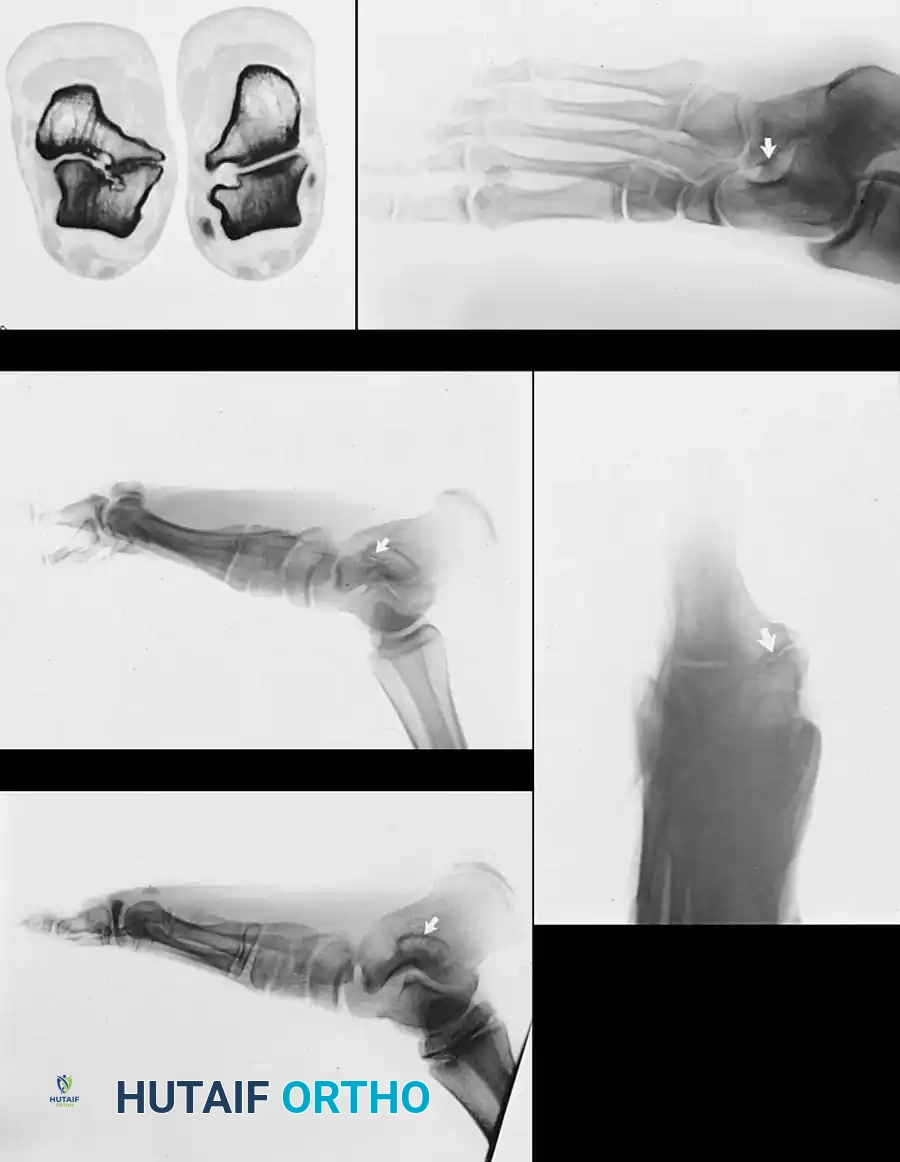

Radiographic Imaging

The 45-degree lateral oblique radiograph is the gold standard for diagnosing a calcaneonavicular coalition. The abnormal bar extends from the anterior process of the calcaneus (just lateral to the anterior facet) dorsally and medially to the lateral/dorsolateral extra-articular surface of the navicular. It typically measures 1 to 2 cm in length and 1 to 1.2 cm in width.

In incomplete coalitions, the adjacent bony margins appear irregular, sclerotic, and indistinct. The talar head may also appear small and underdeveloped.

While standard anteroposterior and lateral radiographs may show secondary signs (such as the "anteater nose" sign for calcaneonavicular coalitions or the "C-sign" and talar beaking for talocalcaneal coalitions), advanced imaging is often utilized in modern practice.

Advanced Imaging and Anatomical Reference Gallery

The following images illustrate various presentations, surgical exposures, and advanced imaging modalities (including CT and MRI correlates) utilized in the comprehensive evaluation and treatment of rigid pes planus and tarsal coalitions: